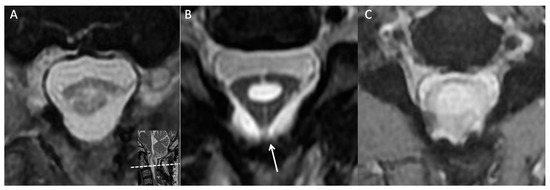

During a review of the patient’s cervical MRI series from previous years, a notable finding was made at the C2 level; that is, a thick arachnoid band was discovered to be attached to the spinal cord and the dural sac, causing the cord to take on a triangular shape in the axial view. This characteristic change in cord shape was termed the “delta cord” sign (Figure 2). Over time, progression of the syrinx from the C2 level to the C4 level was observed. After consideration of potential factors that could contribute to recurrent syringomyelia, postoperative adhesive arachnoiditis was suspected.

Figure 2.

Axial view of the C2 level at multiple time points. (A) Three months after the first surgery. (B) After 1 year, a thick arachnoid band (white arrow) had attached to the posterior aspect of the thecal sac, giving the cord a triangular shape, that is, the “delta cord” sign. Syrinx progression was observed from that point onward. (C) The spinal cord had attached to the thecal sac, and syrinx progression and cord edematous change were observed.

Typically, the arachnoid space is challenging to visualize on MRI because of its woven and loose tubular texture and because it is filled with CSF [23]. However, pathological changes can cause the arachnoid to become thicker and more compact, making it visible on MRI. In the present case, the arachnoid band connecting the spinal cord to the thecal sac initially caused cord distortion, which led to the formation of a triangular shape (Figure 2 and Figure 3). This separation of CSF flow from the cranial and caudal sides resulted in CSF filling the spinal canal and in eventual syrinx formation. Localization signs are valuable for neurosurgeons in that they enable precise surgical plans to be developed and unnecessary exploration of innocent structures to be avoided. Cord tethering, which is often revealed in sagittal views on MRI, is another localization sign [3,11,12,13]. In a Chiari I malformation case with postoperative pseudomeningocele and cord distortion, Belen et al. successfully detethered the spinal cord on the basis of a localization sign and repaired the pseudomeningocele [12]. Clumped root is another reported sign of lumbar adhesive arachnoiditis [3,11].